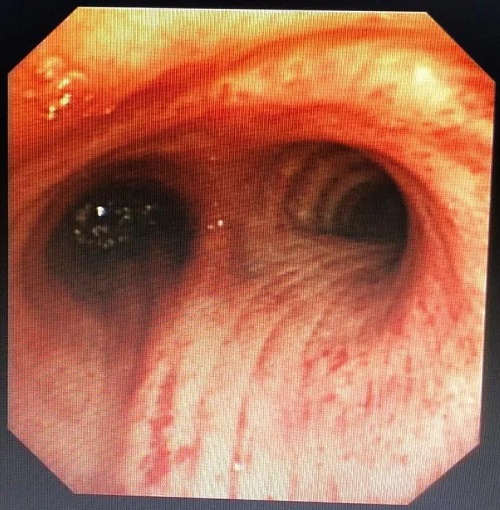

根据术前制定的手术方案,主刀医师应用高频电刀和氩气刀等热消融技术反复对肿瘤行消融治疗。经过1个多小时治疗,切除大部分肿瘤,局部肿瘤根部应用氩气刀止血和消融治疗。

术后患者临床症状明显缓解。呼吸与危重症医学科专家表示,接下来,患者还需要配合其他有效治疗方法,以进一步控制病情。